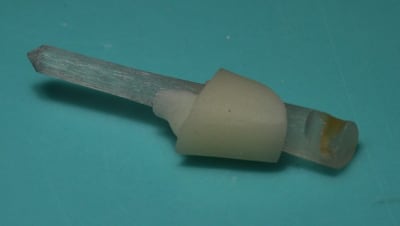

Une variante à la reconstitution à ancrage radiculaire qui donne un excellent résultat mais délicat à effectuer: l'assemblage en bouche par collage d'un pivot en quartz à un inlay-core en emax tunnelisé réalisé au labo.

Mais un inlaycore en céromère directement réalisé au labo avec le pivot en monobloc est évidemment plus pratique.